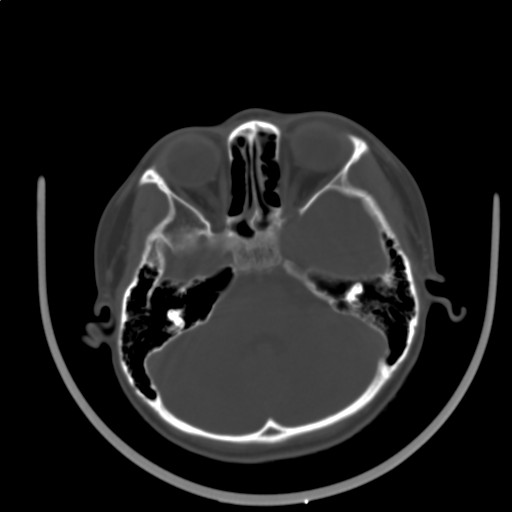

标题: PED3416:F,12Y,智力下降,学习成绩差,8个月时发过高烧。

右侧半球萎缩,软化,多量脑回样钙化,考虑颅面血管瘤病,建议dsa检查

右侧半球萎缩,软化,多量脑回样钙化,同侧颅盖板障增宽,考虑颅面血管瘤病,建议dsa检查与化脓性脑膜炎后遗改变鉴别。